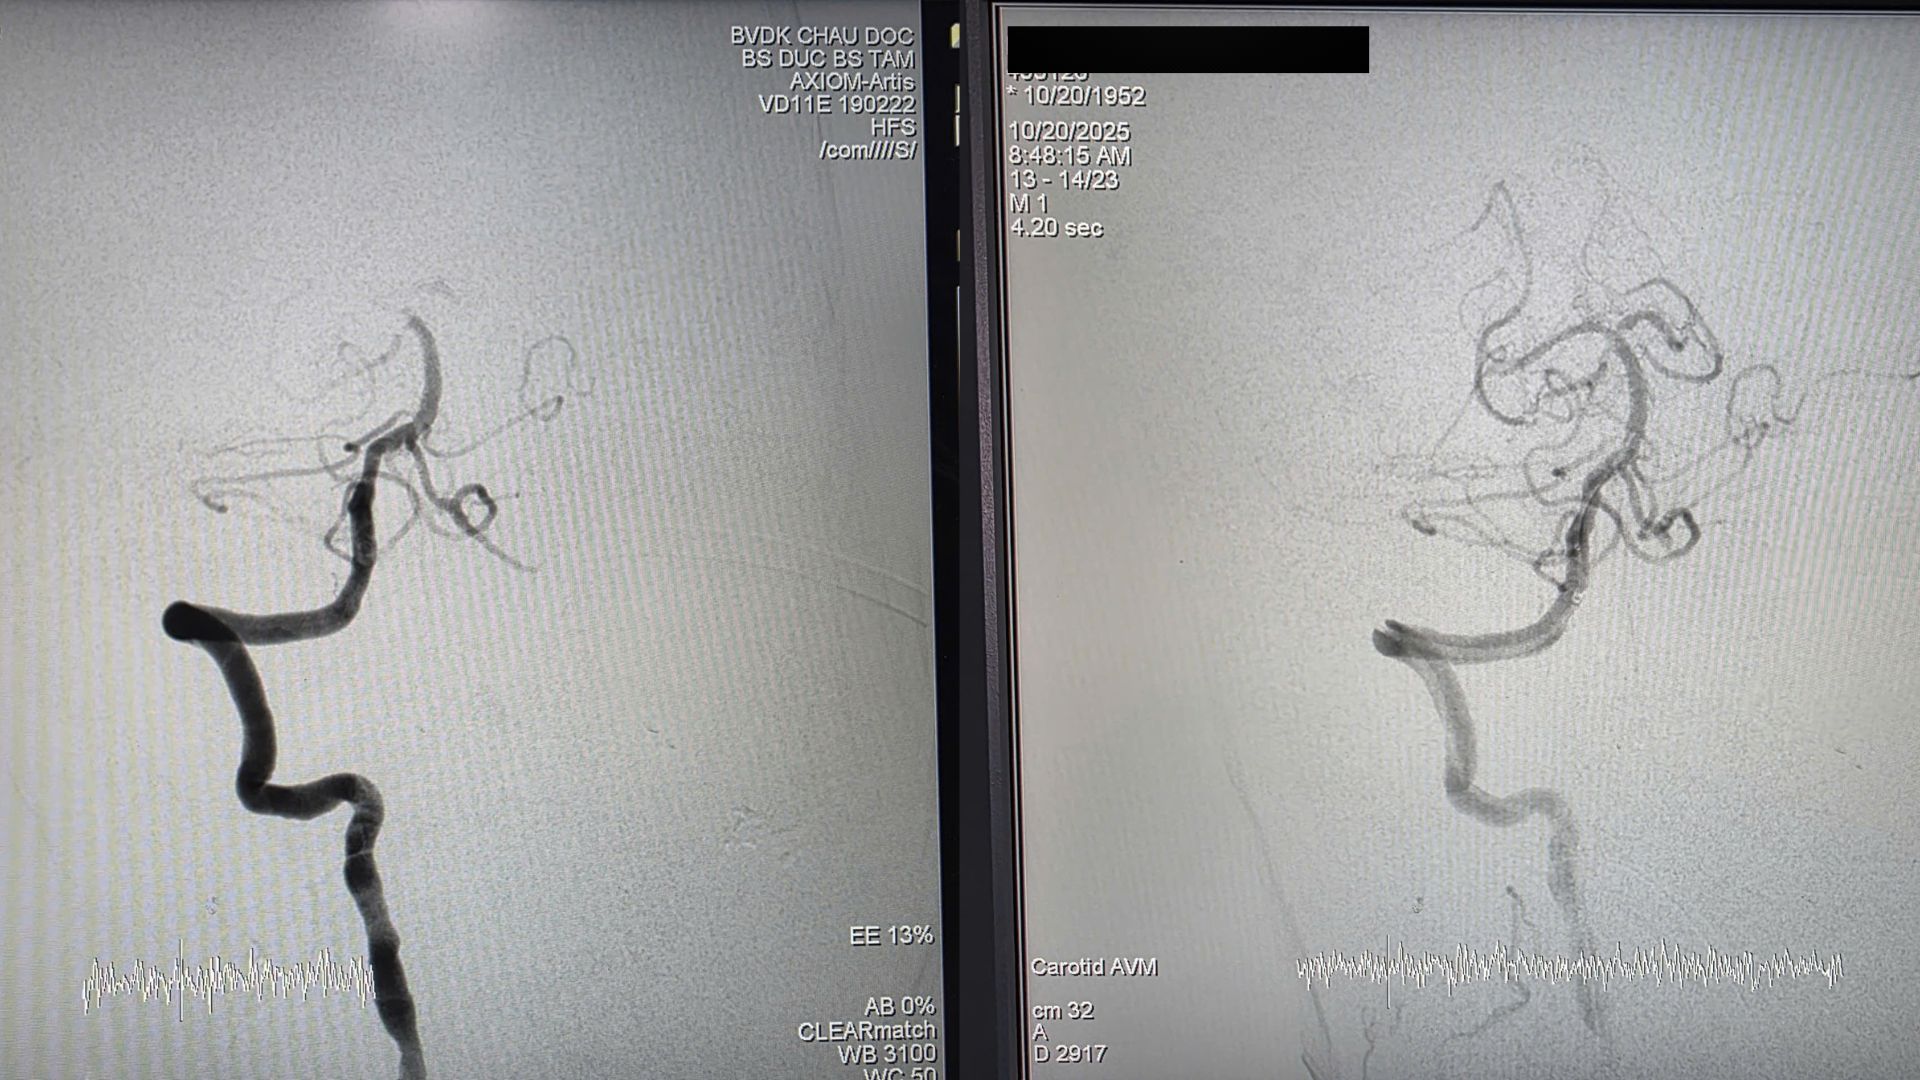

Hình ảnh chụp mạch máu não trước (trái) và sau (phải) can thiệp cho thấy dòng chảy được tái thông sau lấy huyết khối, giúp bệnh nhân hồi phục nhanh chóng (Ảnh: BSCC)

Kết quả chụp CTA cho thấy tắc đỉnh động mạch thân nền (Basilar Artery) – một mạch máu quan trọng dẫn máu đến thân não và tiểu não. Bệnh nhân được chỉ định can thiệp lấy huyết khối cơ học (EVT) khẩn cấp để tái thông mạch.

Sau can thiệp, bệnh nhân tỉnh, trả lời đúng, phục hồi sức cơ tốt và được ngưng thở máy. Đến sáng 22/10, theo xác nhận của BS.CK2 Hà Minh Đức – Trưởng khoa Nội Thần kinh – Đột quỵ, Bệnh viện Đa khoa Châu Đốc, bệnh nhân tỉnh táo, nói chuyện bình thường, sức khỏe cải thiện rõ rệt.

BS.CK2 Hà Minh Đức chia sẻ: “Ở bệnh nhân này có rất nhiều bệnh phối hợp: đột quỵ cấp do tắc động mạch thân nền được tái thông, nhồi máu cơ tim cấp, kèm rung nhĩ cơn. Điều may mắn là bệnh nhân phục hồi tốt sau 24 giờ, hình ảnh CT sau can thiệp gần như không tổn thương nhu mô não“.